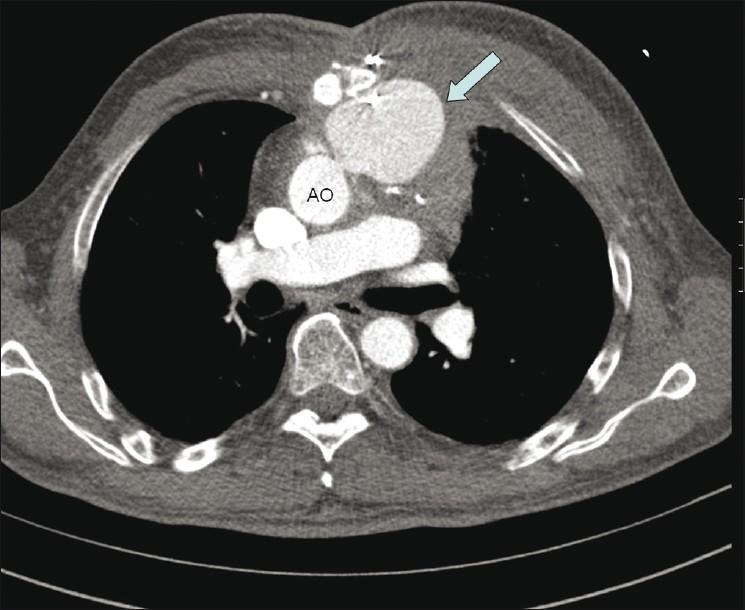

Pseudoaneurysm of ascending aorta is an infrequent but well-recognized and potentially fatal complication after cardiac surgeries. The complication can develop early, delayed or late, and the presentation is also varied. We are presenting here two cases of pseudoaneurysm of ascending aorta following cardiac surgery that were successfully managed by the transcatheter method. The first one occurred following coronary artery bypass surgery and the second one occurred following double-valve replacement surgery. The aortic openings of these aneurysms were occluded with 12 mm and 10 mm atrial septal occluders, respectively, with a good outcome. An immediate postprocedure angiogram showed no residual flow into the sac. Six months of follow-up of both cases also showed excellent results.

升主动脉假性动脉瘤是心脏手术后一种罕见但已被充分认识且可能致命的并发症。该并发症可早期、延迟或晚期发生,表现也各不相同。我们在此呈现两例心脏手术后升主动脉假性动脉瘤病例,均通过经导管方法成功治疗。第一例发生在冠状动脉旁路移植术后,第二例发生在双瓣膜置换术后。这些动脉瘤的主动脉开口分别用12毫米和10毫米的房间隔封堵器封堵,效果良好。术后即刻血管造影显示无血液残留进入瘤腔。两例患者术后6个月的随访结果也都非常理想。